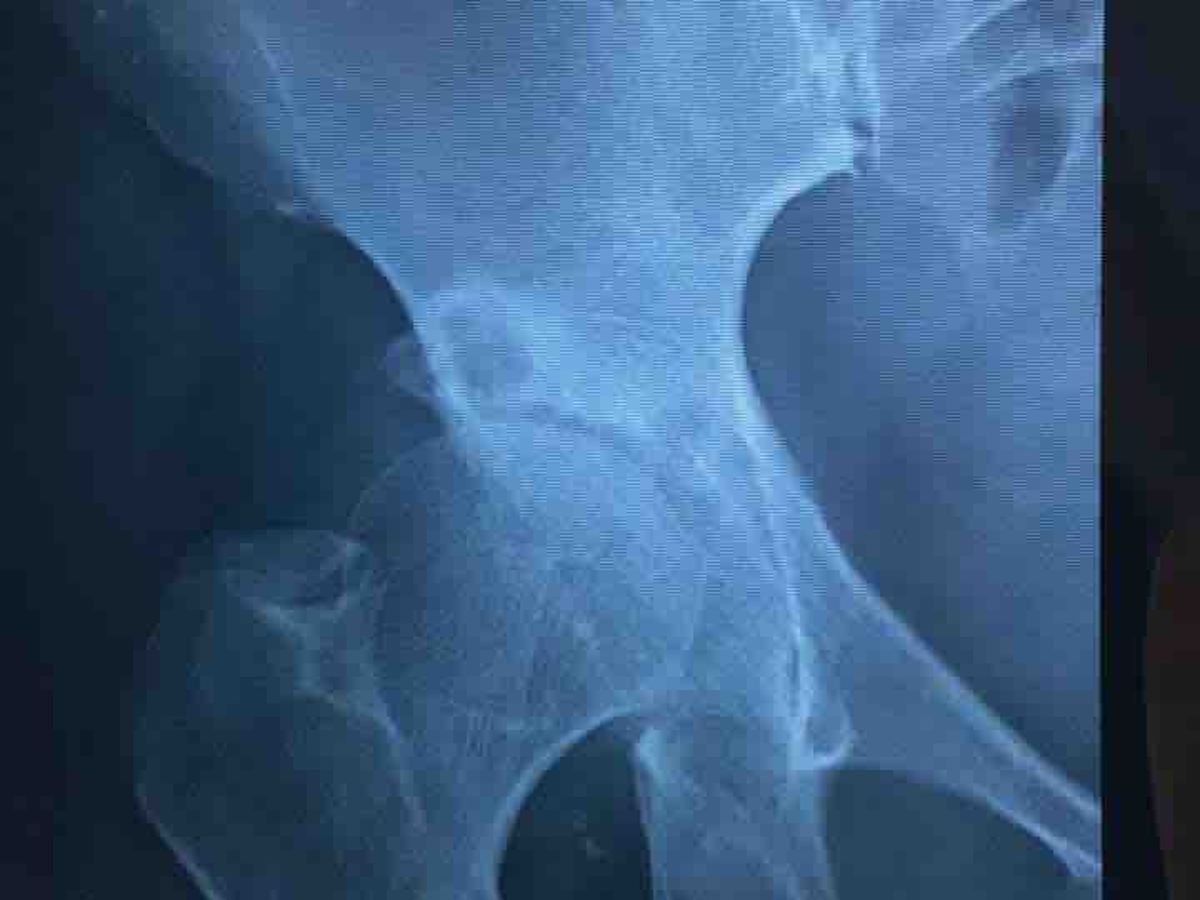

To all my family, friends, friend of friends, colleagues and everyone that can help, this is my friend Gloria. We have known each other for about 10 years now and she resides in El Salvador. She is struggling with medical care expenses, due to COVID-19 restrictions causing her business to shutdown for several months. She moved into our house in Santa Tecla, because she could not continue to pay her own house until she got back on her feet, but now she is faced with another hip surgery, due to a fall earlier in the year when she broke her other hip. Gloria is a very proud person and it took a lot of begging her to allow me to do this for her, because has always been the provider in her family. She is seeing her long time customers and trying to retain her cliental even when she is on crutches and in extreme pain. Her hip surgery, physical therapy and medication costs is going to run over $10k.